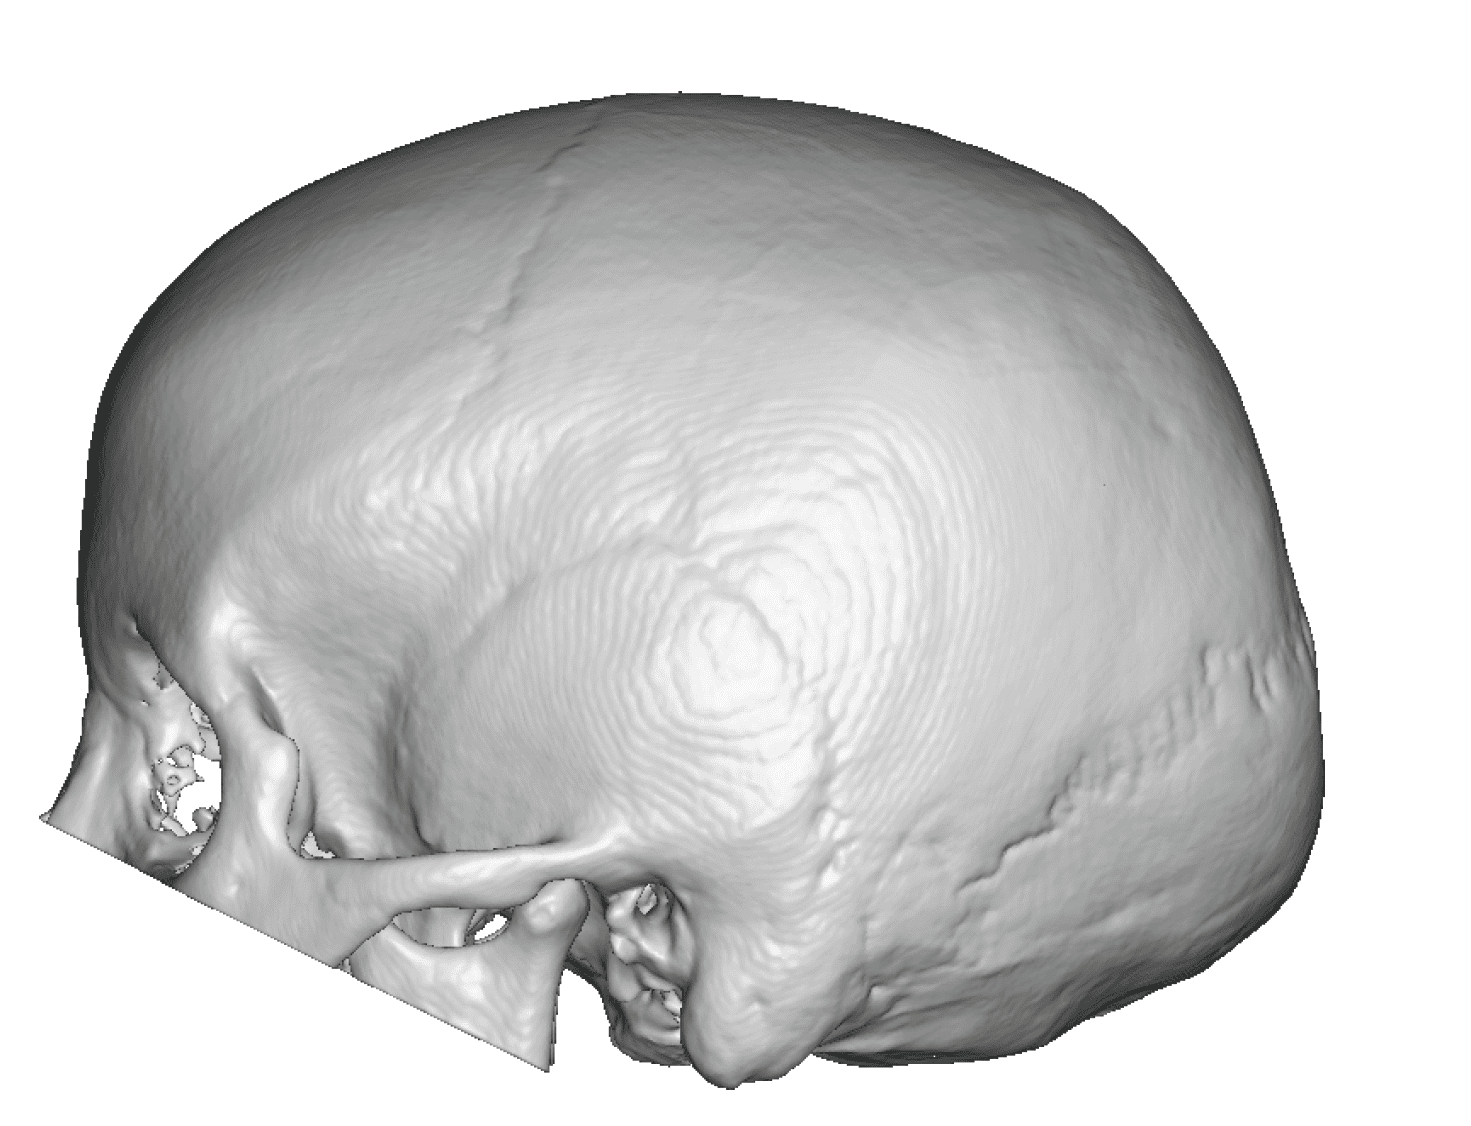

Severe narrowing skull deformity from prior sagittal craniosynostosis repair as an adult.

Complete replacement of entire skull by a custom implant with temporal fat injections.

Severe narrowing skull deformity from prior sagittal craniosynostosis repair as an adult.

Complete replacement of entire skull by a custom implant with temporal fat injections.